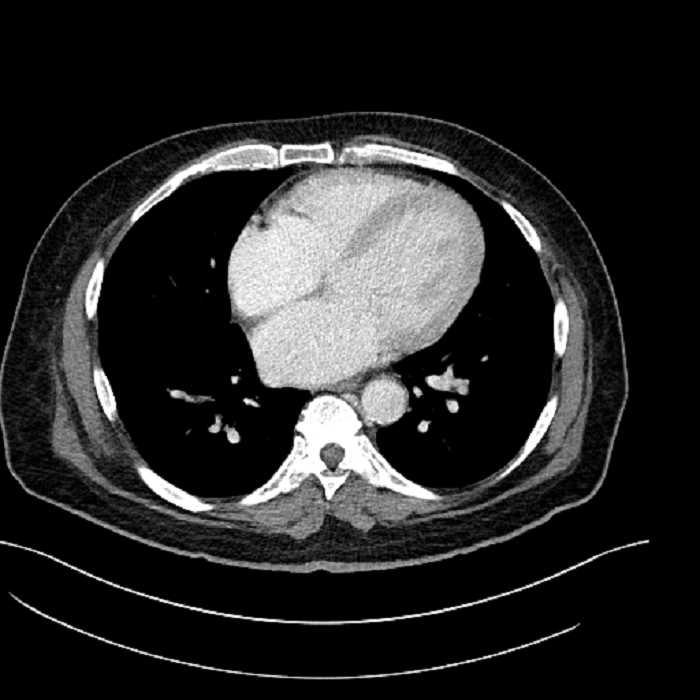

• Lower chest

• Mild cardiomegaly

• Mild dependent atelectasis

Acute sigmoid diverticulitis complicated by a small contained perforation and a large abscess in the right hepatic lobe. Additional small subcapsular abscesses along the anterior margin of the left hepatic lobe.

Hepatic abscess showing the double target sign with low density internally surrounded by a thin inner enhancing rim (red arrow) and ill-defined outer low density rim (yellow arrow). Blue arrow indicates an internal septation. Red arrows: additional smaller subcapsular abscesses. Red arrow: focal contained perforation associated with diverticulitis.